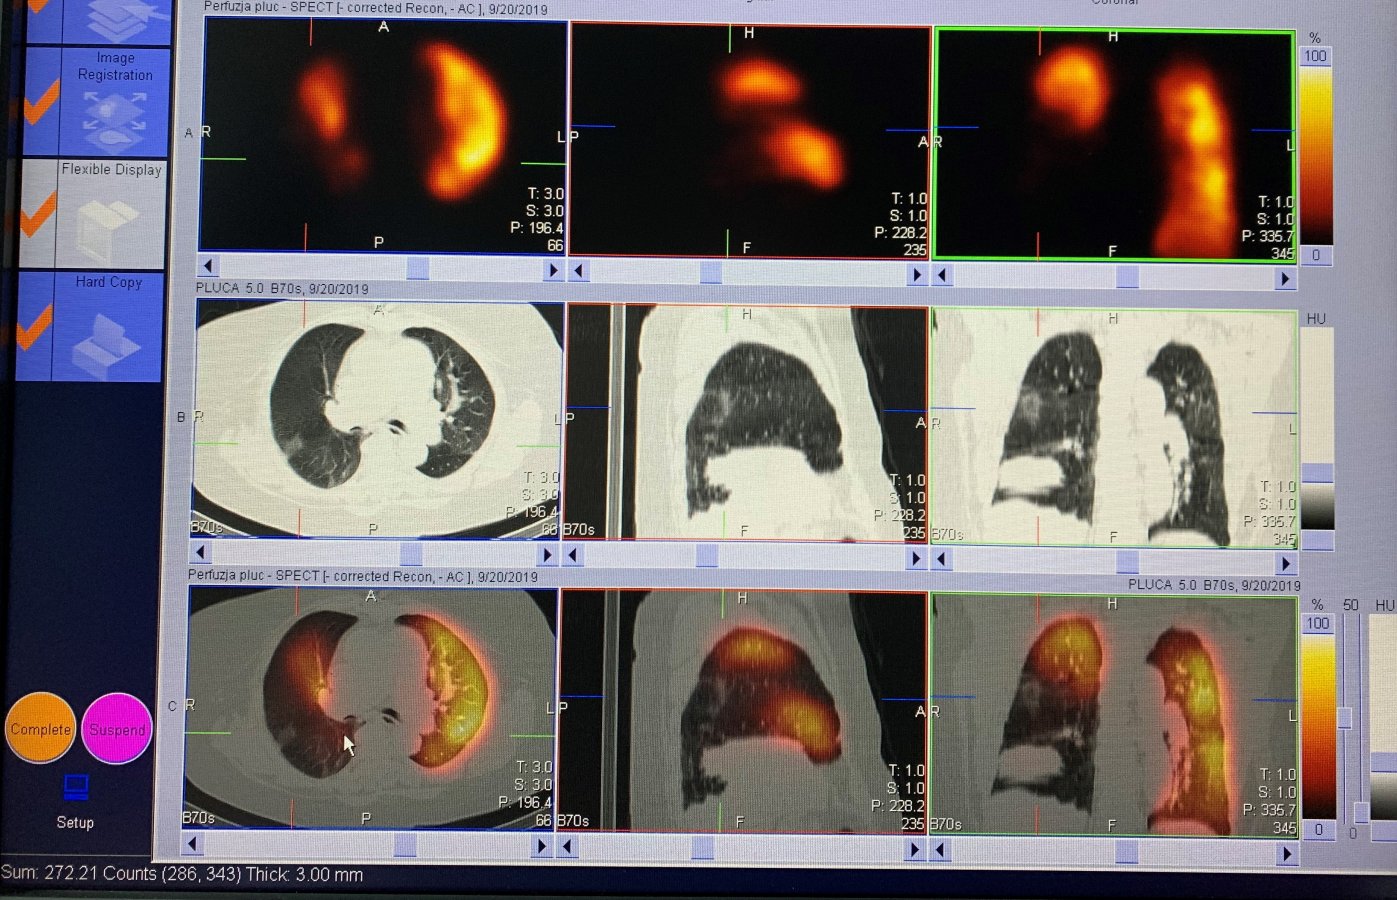

Przykładowe obrazy scyntygraficzne uzyskiwane w naszym Zakładzie Medycyny Nuklearnej: